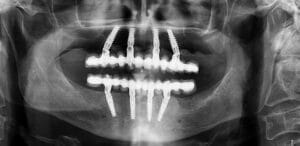

We use a CBCT (cone beam CT) scan alongside digital impressions and photography to create a precise 3D model of your mouth. This allows us to plan your implant placement virtually.

Using a 3D navigation system, our dentists position implants digitally at the perfect angle and depth. This plan is then transferred into a customised surgical guide and if needed temporary teeth, which can be placed directly onto the newly placed implants.

Step 4 – Surgery day

On the day of treatment, you’ll be welcomed into our central London clinic and we will explain the surgery again step by step. Your implant guide ensures the implant is placed in exactly the pre-planned location. Sedation is available for anxious patients who prefer a more relaxed experience.

A dental navigation system is a computer-aided tool that guides dentists during implant placement. It merges CBCT scans with digital impressions to create a virtual 3D model of your mouth. The system then provides real-time guidance so the implant is positioned at the exact angle, depth, and location planned in advance. This improves accuracy, reduces invasiveness, and ensures long-lasting results compared with freehand placement.